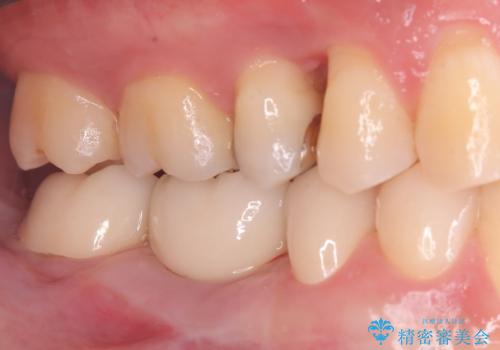

土台となっていた5番と7番は、セラミッククラウンで修復。

インプラントとセラミック修復: 中央の6番にインプラントを埋入し、両隣の5番・7番はそれぞれ独立したセラミッククラウンで修復しました。ブリッジ時代は歯がつながっていたためお手入れが困難でしたが、個別の歯になったことで、一本ずつフロスが通るようになり、セルフケアの精度が劇的に向上しました。

この総合的なアプローチにより、しっかりと噛める機能回復はもちろん、細菌感染に強く、ご自身で隅々までお掃除ができる「健康的な口腔環境」を実現することができました。